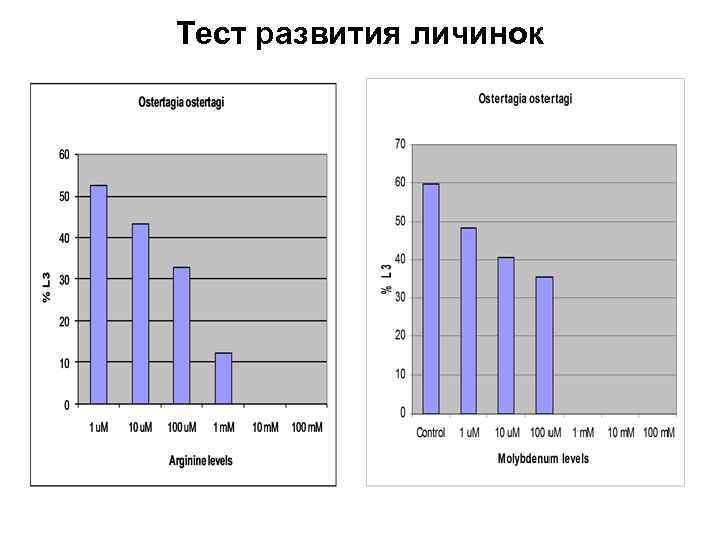

Тест развития личинок